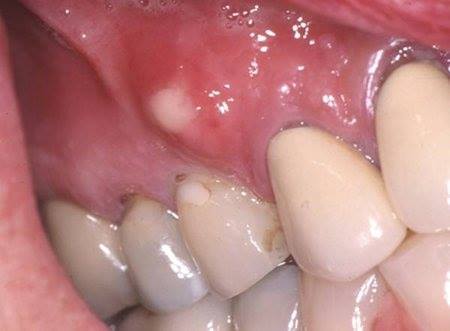

2. SINGNS - SYMPTOMS

1. PAIN EATING

1. BAD TASTE / ODOR IN MOUTH

1. JAW PAIN

1. TOOTH TURNS DARK

1. SWOLLEN FACE